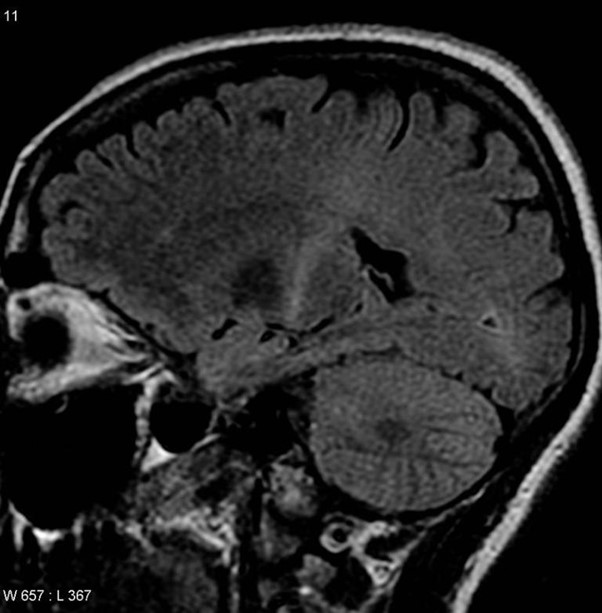

Een MRI met een sterker signaal in het achterste gedeelte van de interne capsule die kan worden getraceerd naar de hersenschors, wat strookt met een ALS-diagnose. Met dank aan: Frank Gaillard/Wikipedia© Aangeboden door Medical Xpress